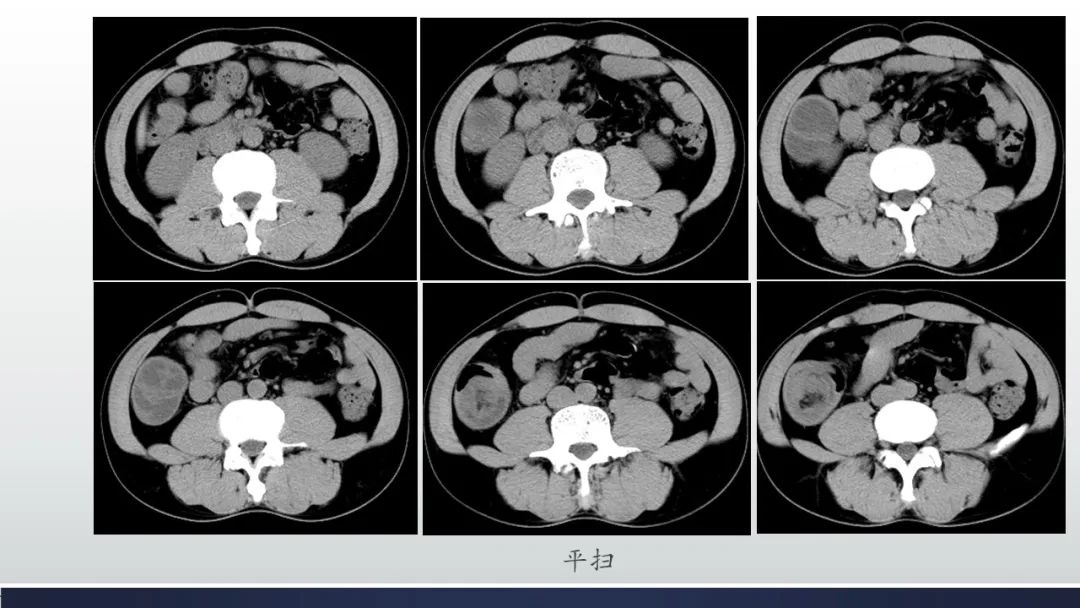

肠壁海绵状淋巴管瘤伴套叠1例CT

张文坦:回结型肠套叠,脂肪瘤或小的小的平滑肌继发可能。

欧鸿儒:肠套叠,冠状位明显见系膜血管卷入,里面有脂肪,不除外合并脂肪瘤。 医学百科网 | YxBaike.Com

徐纲:同心圆,内见脂肪,脂肪瘤并肠套叠?

王鑫:中老年男性,成年人肠套叠,多伴有肿瘤或肿瘤样病变,套叠处肠壁厚薄不均,虽没有明确异常强化分界区,仍需考虑伴有肿瘤可能

刘祥:肠套叠,考虑末段回肠脂肪瘤所致 医学百科网 | YxBaike.Com